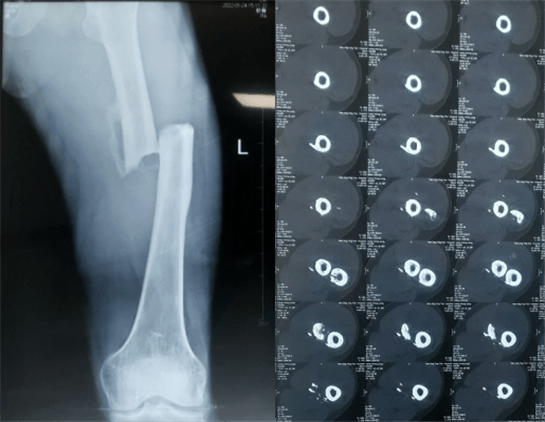

患者:男性,43歲,左股骨干骨折髓內(nèi)釘內(nèi)固定術(shù)

醫(yī)院:南京應(yīng)天骨科醫(yī)院

股骨是下肢的主要負重骨,有其特殊的解剖關(guān)系,周圍肌肉發(fā)達,因此一旦股骨干骨折后如果治療不當,容易造成肌肉牽拉,導致畸形和功能障礙。治療股骨干骨折,必須遵循恢復肢體的長度及力線,無旋轉(zhuǎn),盡量行以微創(chuàng),保護骨折局部血運,促進愈合。髓內(nèi)釘對骨折的固定能夠達到較大的穩(wěn)定性和堅固性,可以減少醫(yī)源性污染,減少軟組織分離及周圍血供破壞,有利于骨折早期愈合,是治療股骨干骨折的首要治療方法。

術(shù)前檢查